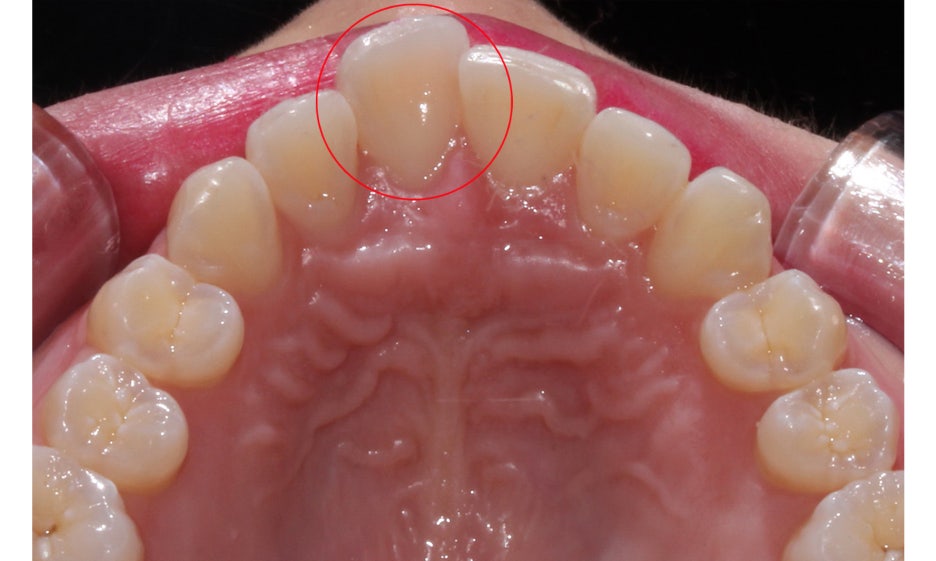

뻐드렁니교정 전 중절치의 모습을 보면

주변 치아들보다 확연하게 순측으로

튀어나와 있는 것을 확인할 수 있는데요,

치아가 돌출된 만큼 전치부의

overjet 수치가 커지게 됩니다.

확인할 수 있는 측정 방법으로

상악 최전방 치아에서

하악 최전방 치아 사이의 수평거리를

측정하게 확인할 수 있습니다.

일반적인 경우 overjet 수치는

2~3mm 정도로 나타나는데요,

돌출이 있는 경우 이보다 크게 측정될 수 있습니다.

뻐드렁니교정 전 상악의 교합면을 보면

11번치아(좌측 중절치)가 입술 방향으로

튀어나와 있는 모습을 확인할 수 있는데요,

악궁의 길이가 짧은 경우 치아가 배열될 수 있는

공간이 부족해지면서 위와 같은 증상이 나타날 수 있습니다.